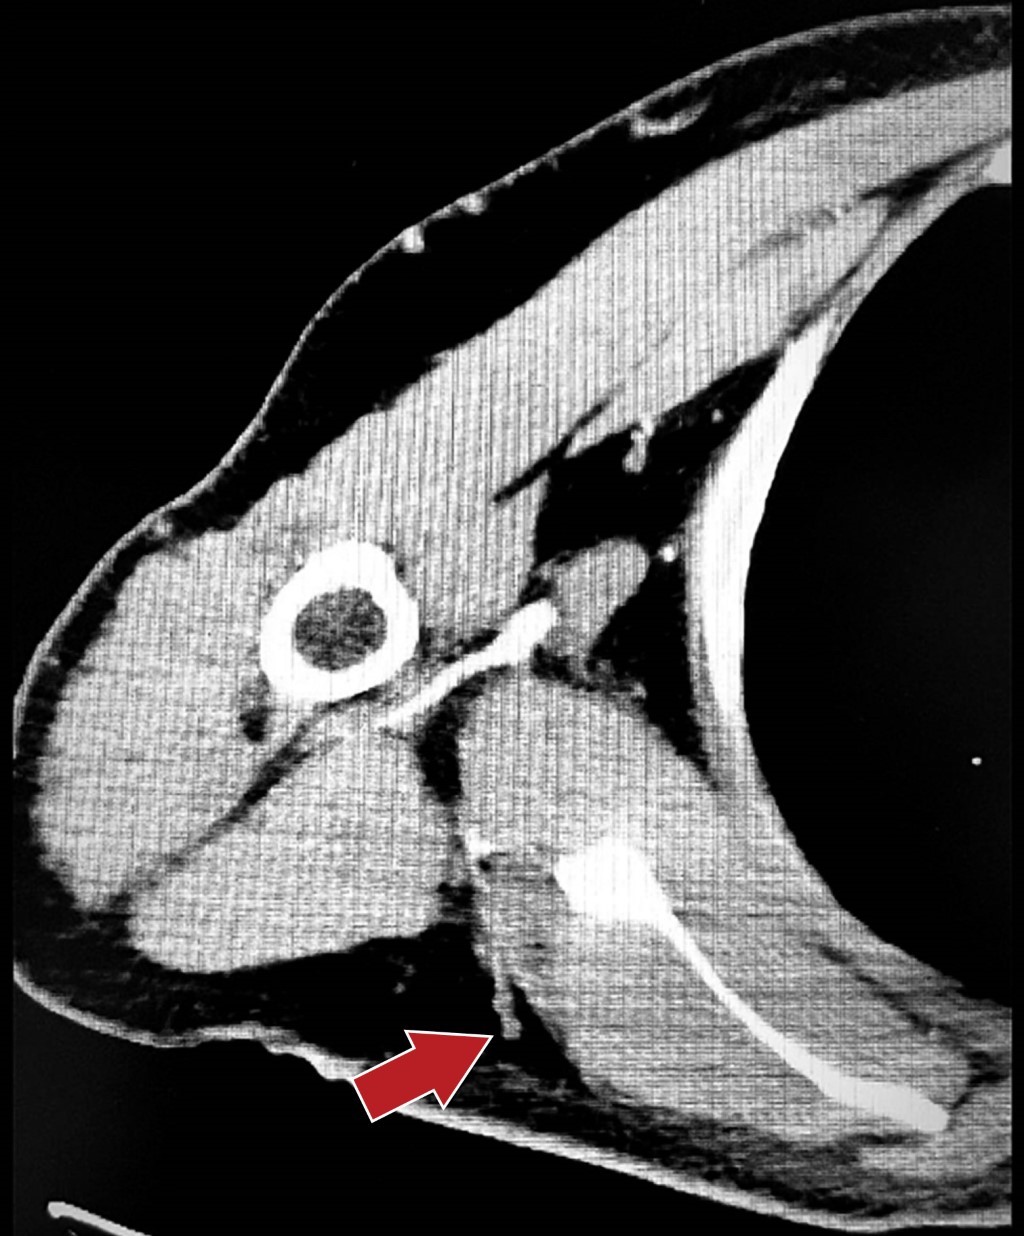

Caso 3. Hombre de 53 años con diagnóstico de sarcoma fibromixoide en hombro derecho, antecedente de una resección amplia previa, el cual fue reconstruido con colgajo de trapecio. Se realiza mapeo de perforante con tomografía computarizada contrastada y ultrasonido Doppler (Figura 4). Posterior a la resección amplia y procedimiento de Tikhoff-Linberg por cirugía oncológica, se observa un área cruenta de 20 × 20 cm en el hombro, con exposición parcial de articulación acromioclavicular y escápula. Se levanta colgajo de 15 × 20 cm para reconstrucción de la superficie más lateral de defecto; en el resto del defecto medial y el área donadora de colgajo, se realizó cierre primario. Después de la disección del colgajo TDAP se realizó su rotación en propela a 180°. Durante el seguimiento el paciente desarrolló dehiscencia de 1 cm en el área donadora, la cual cicatrizó por segunda intención. El seguimiento a siete meses demuestra una limitación funcional del hombro para la abducción debido al procedimiento de Tikhoff-Linberg; sin embargo, el paciente es capaz de realizar sus actividades cotidianas. Sin otras complicaciones (Figura 5).

Recomendamos el uso de ultrasonido Doppler para mapeo de las perforantes, lo que ayuda al diseño del colgajo; se debe incluir la zona con más perforantes en el diseño de la isla de piel. En el caso 3, mostramos el mapeo realizado con ayuda de una tomografía axial contrastada, lo que ayudó a su diseño (Figura 5). Diseñamos la isla de piel en sentido vertical, debido a que con esto se logra una mayor longitud de la isla cutánea, característica deseada sobre todo en este caso.4 Durante la cirugía, en los tres pacientes se logró observar por lo menos una perforante, la cual era mayor a 0.5 mm y con pulso visible.